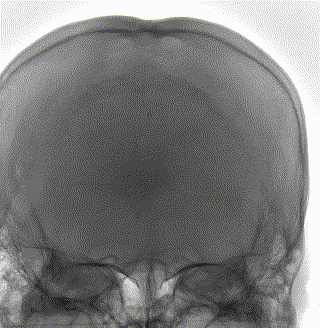

头MRI+MRV:左侧橫窦、乙状窦走形区异常信号,考虑为血栓。